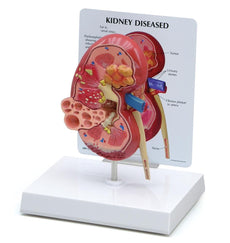

This Urinary System all-in-one-model shows:- Structures of retroperitoneal cavity

- Large and small pelvis with bones and muscles

- Inferior vena cava

- Aorta with its branches including iliacal vessels

- Upper urinary tract

- Rectum

- Kidney with adrenal gland.

One front half of a kidney is removable from the anatomical model of the urinary system. With easy to change male insert (bladder and prostate, front and rear half) and female insert (bladder, womb and ovaries, 2 lateral halves) the Urinary System model is a great teaching tool.